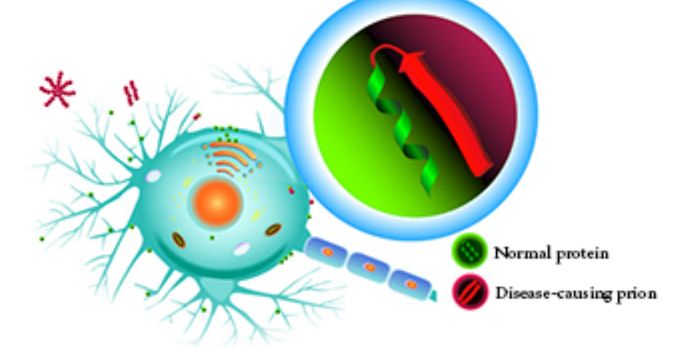

JAN 31, 2016Clinical & Molecular DXNo, you can’t catch Alzheimer’s like you could a cold. But new evidence suggests Alzheimer’s may be tr ...

JAN 14, 2016Clinical & Molecular DXAlzheimer’s disease is highly prevalent, accounting for over 7 million new cases every year. While there’s n ...

NOV 10, 2017MicrobiologyChronic wasting disease (CWD) is a contagious neurological disorder that affects deer, elk, reindeer, and moose that lea ...